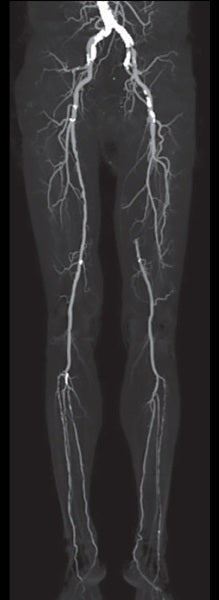

比較的若年のSFA-CTO症例であったが、患者は低侵襲であるEVTを希望された。 仕事が多忙とのことであり、何度もEVTを行うのは難しい状況のため、できるだけバイアバーン® ステントグラフト留置によって長期開存が得られるよう十分な内腔の確保、healthy landingを念頭に、将来的に万一閉塞した場合に備えて側副血行路の温存を考えた。(図1、2)

- 対象病変部位 : 左 EIA: 90%、 左 SFA ostium 〜 distal CTO

- TASC Ⅱ分類 : C

- 病変長 : 22 cm

術前のCTAでは左EIAに高度狭窄を認めたため、対側CFAアプローチとした。腸骨動脈領域はびまん性高度石灰化を伴っていたが、大腿膝窩領域にはSFA遠位部にスポットな石灰化を認めるのみであった。CTOに対するワイヤリングに際して、当院では使用するデバイスの種類にかかわらず十分なデバイス拡張を得るためにIVUSガイドワイヤリングを行い、intraplaqueを通過するよう心がけている。ただし、本症例は心房細動の既往もあり血栓性病変である可能性も考えられたため、ガイドワイヤー通過後にIVUSでプラークの診断を行い、必要があれば末梢保護デバイスの使用を考慮することとした。